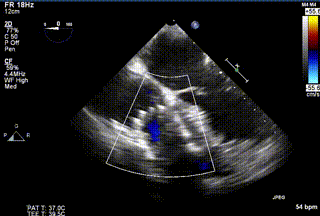

2021年12月24日,復(fù)旦大學(xué)附屬中山醫(yī)院葛均波院士團(tuán)隊(duì)成功應(yīng)用LuX-Valve Plus為一例極重度三尖瓣反流(TR)合并房顫、房缺的患者完成了經(jīng)血管三尖瓣置換術(shù),這是在前基礎(chǔ)上,本周完成的第三例經(jīng)血管三尖瓣置換手術(shù),葛均波院士、周達(dá)新教授等與心外科魏來(lái)教授、賴顥教授,心超室的潘翠珍教授、李偉教授及麻醉科的郭克芳教授共同完成了本周手術(shù),均獲得圓滿成功!患者術(shù)后超聲顯示無(wú)TR,臨床癥狀明顯改善。本周手術(shù)的成功也為L(zhǎng)uX-Valve Plus救治性臨床研究添上了濃墨重彩的一筆。

三例患者入院后,葛均波院士團(tuán)隊(duì)周達(dá)新教授、潘文志教授、張?jiān)床┦?、陳莎莎博士及心超室的潘翠珍教授、李偉教?/strong>對(duì)患者的情況進(jìn)行詳細(xì)評(píng)估和討論,最終決定為三例患者選擇LuX-Valve Plus40mm、50mm和50mm型號(hào)的瓣膜進(jìn)行手術(shù)治療。手術(shù)后即刻拔除氣管插管,術(shù)后患者三尖瓣反流癥狀得到顯著改善,復(fù)查心超結(jié)果顯示人工三尖瓣瓣膜支架固定穩(wěn)定,瓣葉關(guān)閉形態(tài)未見(jiàn)異常,未見(jiàn)明顯反流。